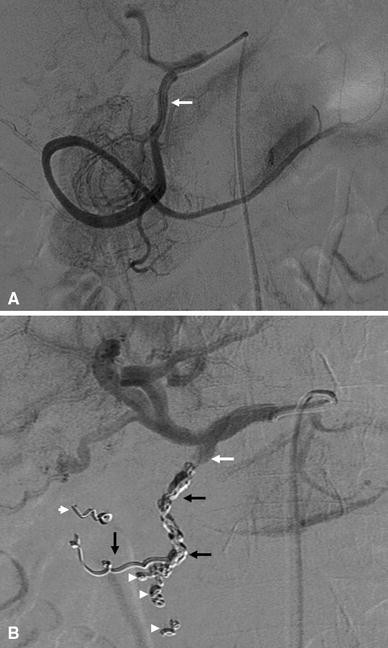

Fig. 2

Angiographic images demonstrating empiric embolization of the GDA. A Selective angiography of the GDA (white arrows) before embolization showing no evidence of active bleeding. B Selective angiography of the GDA after coil embolization of the distal and proximal GDA (black arrows), including the anterior and posterior superior pancreaticoduodenal arteries and the right gastroepiploic artery, to prevent retrograde flow (white arrowheads)